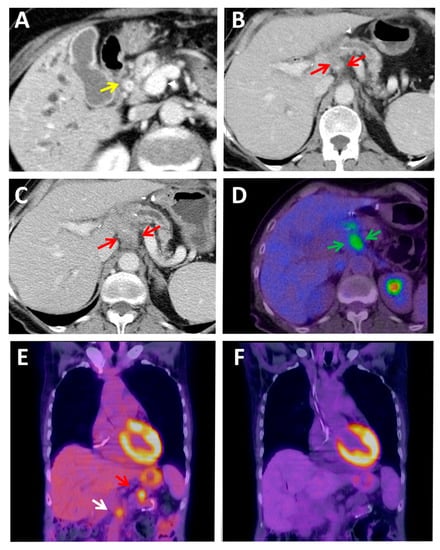

2.4. PET Hybrid Imaging

3.2. The Current Status of Immuno-PET in PDAC